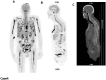

The International Myeloma Working Group (IMWG)recommends FDG PET/CT (Fluoro-Deoxy-glucose Positron Emission Tomography/Computed Tomography) as the gold standard imaging modality for initial evaluation and response to therapy assessment in multiple myeloma. In fact, FDG PET/CT, provides multiple useful indexes to risk-stratify patients and has significant prognostic value. However, multiple myeloma remains a complex disease to interpret on imaging. The Italian myeloma criteria for PET use (IMPeTUs) were proposed to standardize FDG PET/CT reading in multiple myeloma. In this communication an overview on IMPeTUs is provided as well as some examples of application.